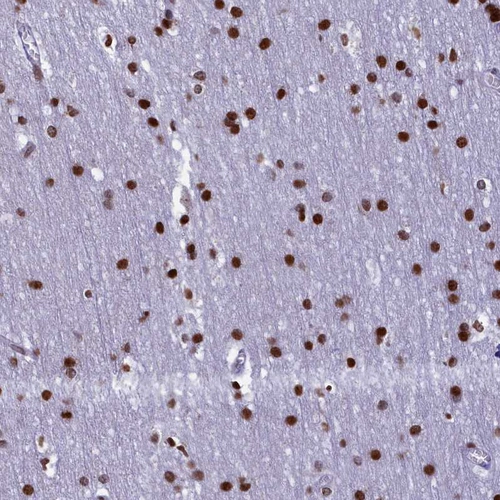

Immunohistochemical staining of human cerebral cortex shows strong nuclear positivity in glial cells.